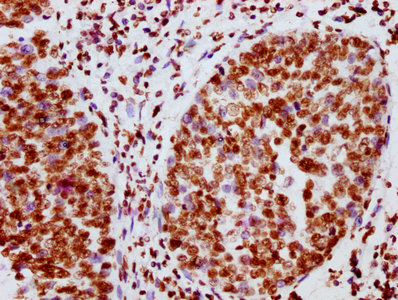

IHC image of CSB-RA011931A100phHU diluted at 1:100 and staining in paraffin-embedded human ovarian cancer performed on a Leica BondTM system. After dewaxing and hydration, antigen retrieval was mediated by high pressure in a citrate buffer (pH 6.0). Section was blocked with 10% normal goat serum 30min at RT. Then primary antibody (1% BSA) was incubated at 4℃ overnight. The primary is detected by a biotinylated secondary antibody and visualized using an HRP conjugated SP system.

IHC image of CSB-RA011931A100phHU diluted at 1:100 and staining in paraffin-embedded human cervical cancer performed on a Leica BondTM system. After dewaxing and hydration, antigen retrieval was mediated by high pressure in a citrate buffer (pH 6.0). Section was blocked with 10% normal goat serum 30min at RT. Then primary antibody (1% BSA) was incubated at 4℃ overnight. The primary is detected by a biotinylated secondary antibody and visualized using an HRP conjugated SP system.